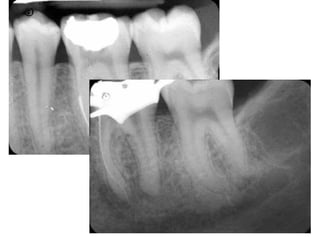

OBTURATION

UNDERFILLING

OVERFILLING